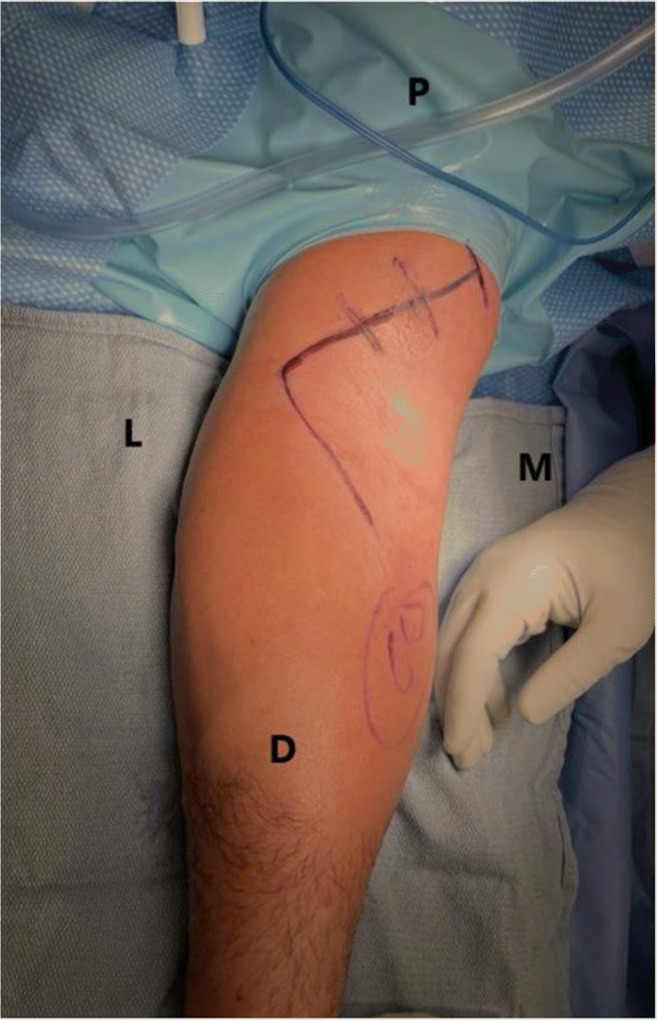

Figure 5.

An anterior oblique incision is used to identify the tendon. The incision can be extended proximally for retracted tendons and distally when the lacertus fibrosus is intact and the tendon lies more distally

The Arthrex Distal Biceps Repair Kit (Arthrex, Naples, FL, USA) has been recently introduced and it provides all the tools for an anatomic posterior approach repair using 2 cortical intramedullary buttons (Fig. 4). An oblique anterior incision is used to find the tendon proximally. If the lacertus fibrosus is intact, the incision can be extended distally around the elbow flexion crease laterally (Fig. 5). Identify the LACN and neurolysis may be needed if the nerve is surrounded by scar tissue. The distal tendon is often encased in pseudo tendon. The scar is removed from the distal tendon end to expose the short and long heads to ensure proper tendon alignment. A four-throw modified Krackow whipstitch is placed in each head. The outside limb of the stitch is locked, and the stitch ends 5 to 10 mm from the tendon end on the dorsal side. The central limb of the suture on each head is placed in a simple running pattern and finishes in the center of each head on the palmar side (Fig. 6A, B).